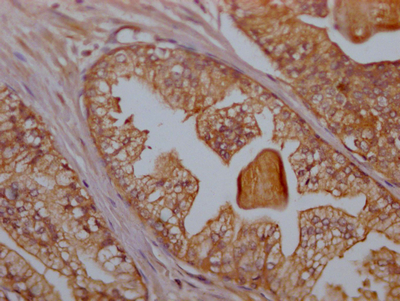

IHC image of CSB-RA802124A0HU diluted at 1:100 and staining in paraffin-embedded human prostate cancer performed on a Leica BondTM system. After dewaxing and hydration, antigen retrieval was mediated by high pressure in a citrate buffer (pH 6.0). Section was blocked with 10% normal goat serum 30min at RT. Then primary antibody (1% BSA) was incubated at 4℃ overnight. The primary is detected by a Goat anti-rabbit IgG polymer labeled by HRP and visualized using 0.05% DAB.